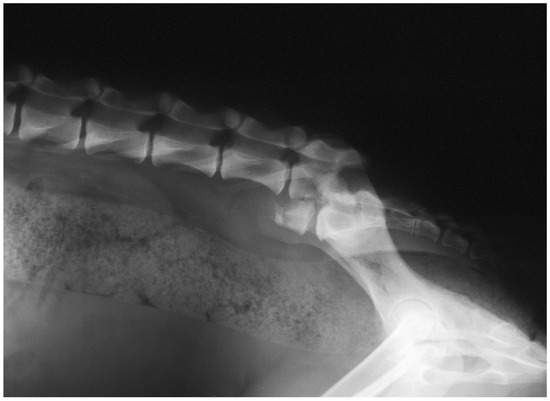

3.4. Imaging

3.5. Treatment